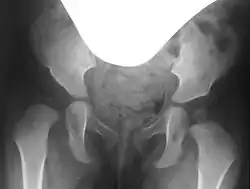

Präoperativ werden sowohl zur genauen Beurteilung der Gelenkfehlstellung und des Schweregrades als auch zur Planung der Operation selbst konventionelle Röntgenbilder des Beckens, sogenannte Beckenübersichtsaufnahmen und Rippstein-Aufnahmen, angefertigt. Die Rippstein-Aufnahmen dienen der genaueren Beurteilung der Schenkelhälse in einer seitlichen Projektion.[4][5]